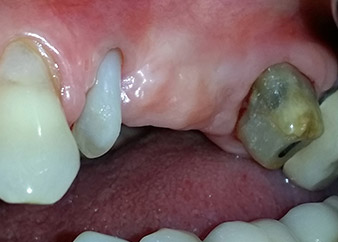

Eine 58-jährige Patientin, die auch eine gute Freundin und ärztliche Kollegin ist, beschwerte sich über Schmerzen und erhöhte Beweglichkeit ihres Brückenpfeilers 24. Es lag auch eine parodontale Entzündung vor, mit Taschentiefen von 7 mm mesiobukkal und mehr als 12 mm distal und einer Furkationsbeteiligung dritten Grades. Darüber hinaus zeigte die Röntgenaufnahme eine großflächige apikale Aufhellung am endodontisch (alio loco) vorbehandelten Zahn 24 (Abb. 1).

Ein Jahr zuvor waren die Zähne 25 und 26 vor dem Einsetzen der Brücke aufgrund traumatischer und endoparodontaler Ursachen extrahiert worden. Eine Paro-Endo-Läsion wurde bei unklarer ätiologischer Hauptkomponente für den Zahn 24 diagnostiziert. Die Patientin machte deutlich, dass sie ihre Pfeilerzähne 24 und 27 behalten und keinen endgültigen oder temporären herausnehmbaren Zahnersatz akzeptieren will. Darum wurde vereinbart, alles zu versuchen, beide Zähne, trotz der nach den radiologischen und klinischen Befunden als schlecht einzustufenden Prognose, zu erhalten.